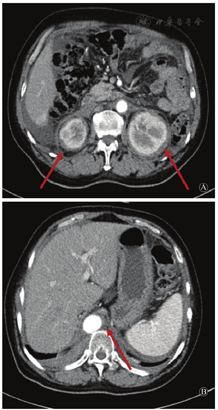

ECD由Erdheim和Chester于1930年首次报道,是一种罕见的非朗格汉斯组织细胞疾病,发病率<5/百万,多见于成年人,男性稍多于女性。ECD的病理基础是富含脂质的组织细胞浸润各器官。最常见的特征是多发的长骨骨质硬化性病变(发生率占95%),伴或不伴骨外组织细胞浸润。临床表现从无症状到致死性的系统疾病,可涉及几乎所有脏器。当症状局限时,患者可仅表现为下肢骨疼痛。几乎一半以上的患者会出现骨外多系统疾病表现。心脏受累是预后不良的首要因素,主要表现包括心包心肌浸润、心房或房室沟肿物,可出现心衰、心肌梗死、瓣膜病、房室传导阻滞、病理性Q波等表现。超过50%的患者出现BRAF V600E基因突变,90%的患者出现MAPK/ERK通路相关基因突变。常见受累脏器见表1,其中,当病变侵犯肾周筋膜时,CT表现为双侧对称的肾周软组织密度影,边界不规则,呈特征性"毛发肾征"(hairy kidney)表现(图2A);当病变包绕整段主动脉时,CT可表现为特征性"主动脉鞘征"(coated aorta)(图2B)。如临床遇到可疑病例,建议行18F-FDG PET/CT检查,评估受累组织范围,再行受累组织活检,并完善组织BRAF V600E突变基因检测,可考虑行MAPK通路或其他突变测序。ECD的典型病理表现是大量泡沫样(黄瘤)组织细胞浸润,间杂炎症细胞和多核巨细胞浸润。ECD细胞表达组织细胞标志物CD68、CD163,不表达CD1a和S100,可通过细胞形态学及免疫组化与朗格汉组织细胞增多症鉴别。此外,需要与IgG4相关性疾病、淋巴瘤、髓系肉瘤、结核感染等疾病鉴别。治疗方面,尚无标准治疗方案,目前最为常用的药物是干扰素a,干扰素治疗的患者5年总生存率约为70%,因多数患者检测出组织中BRAF V600E突变,BRAF抑制剂威罗非尼也越来越广泛地被应用于ECD的治疗[2]。

A:肾周软组织密度影,为"毛发肾"征(箭头所示);B:"主动脉鞘"征(箭头所示)